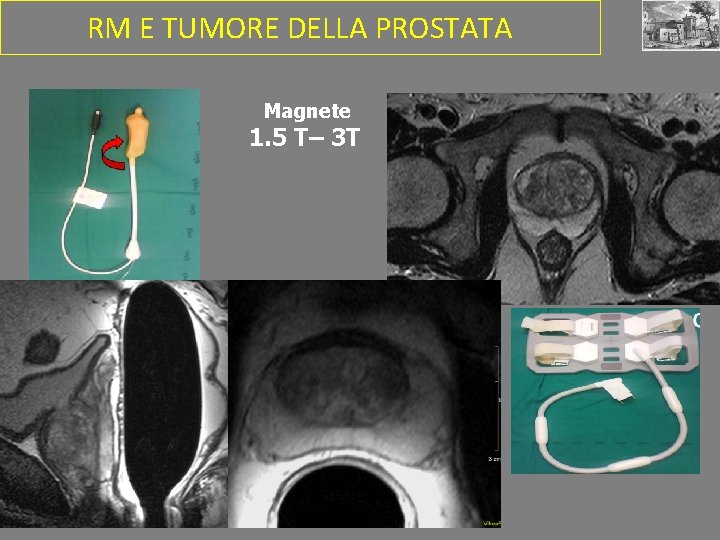

RM E TUMORE DELLA PROSTATA IMAGING DI STADIAZIONE: • Dimensioni tumore • Infiltrazione strutture adiacenti • Interessamento linfonodale IMPOSTAZIONE TRATTAMENTO (CHIRURGIA vs RADIO-CHEMIOTERAPIA)

RM E TUMORE DELLA PROSTATA Magnete 1. 5 T– 3 T